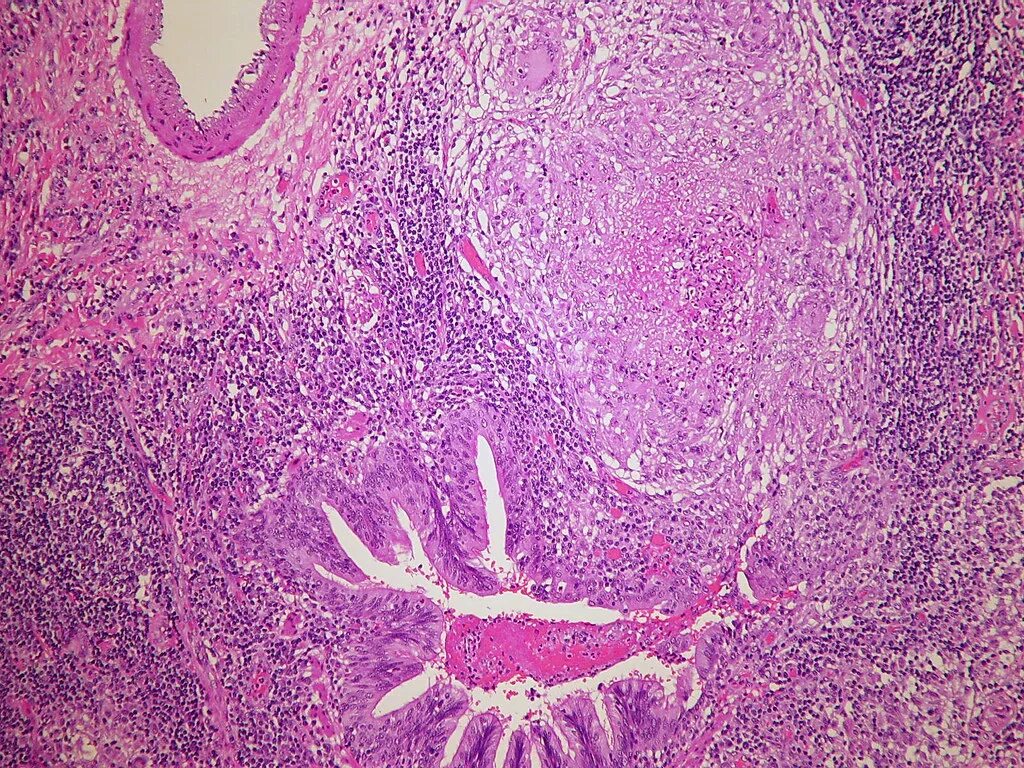

Гистология фото